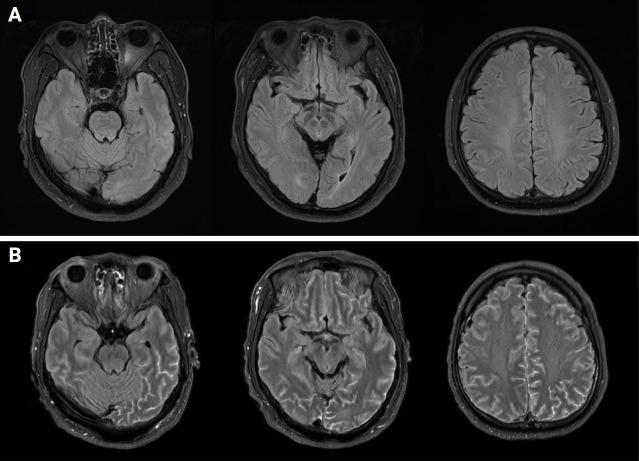

Severe fever with thrombocytopenia syndrome (SFTS) is a potentially fatal infectious disease if not diagnosed and treated promptly. Typical clinical features include fever, thrombocytopenia, and lymphadenopathy. However, we encountered a case of SFTS in a 60-year-old male who initially did not exhibit these hallmark symptoms. The patient presented with headache and myalgia, but fever did not develop until the 4th day of hospitalization. Initial neuroimaging and cerebrospinal fluid (CSF) analysis revealed no abnormalities. When the fever emerged, follow-up imaging revealed findings consistent with meningitis as a complication of SFTS. The patient was successfully treated with antibiotics and made a full recovery. This case underscores the challenges in diagnosing SFTS in patients who lack fever, CSF pleocytosis, or typical neuroimaging findings at presentation. Additionally, it highlights the importance of differentiating SFTS-related meningitis from other causes of encephalitis to avoid inappropriate treatments, such as immunosuppressive therapy, which could worsen viral infections.